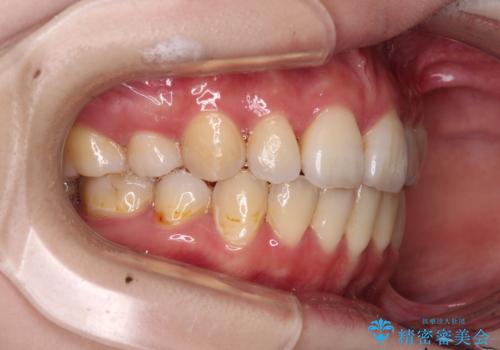

- 口元の突出感を気にして来院された患者様です。

上下左右の第一小臼歯4本を抜歯して口元を下げる治療計画としました。

裏側矯正特有の抜歯スペースに前後の歯が倒れ込む状態が長く続き、改善に長期間を要しました。